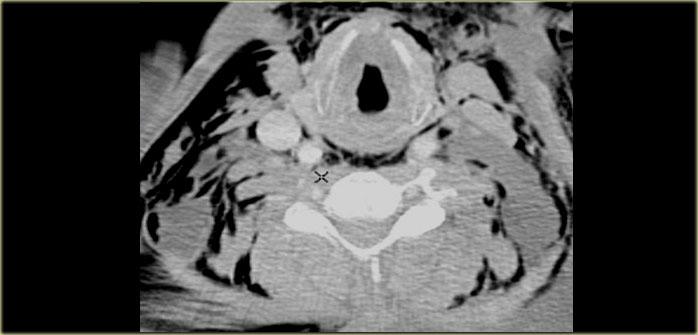

Lát cắt CT ở mức thanh quản trên thanh môn và sụn giáp.

Phía trước sụn giáp là các cơ dây đai (strap muscles): cơ ức giáp, cơ ức móng, cơ giáp móng và cơ vai móng.

Tất cả các cơ này đều bám vào xương móng và có chức năng hạ thấp xương móng và thanh quản trong quá trình nuốt và nói.

Các cơ này dài và dẹt, có hình dạng tương tự như một chiếc dây đai.